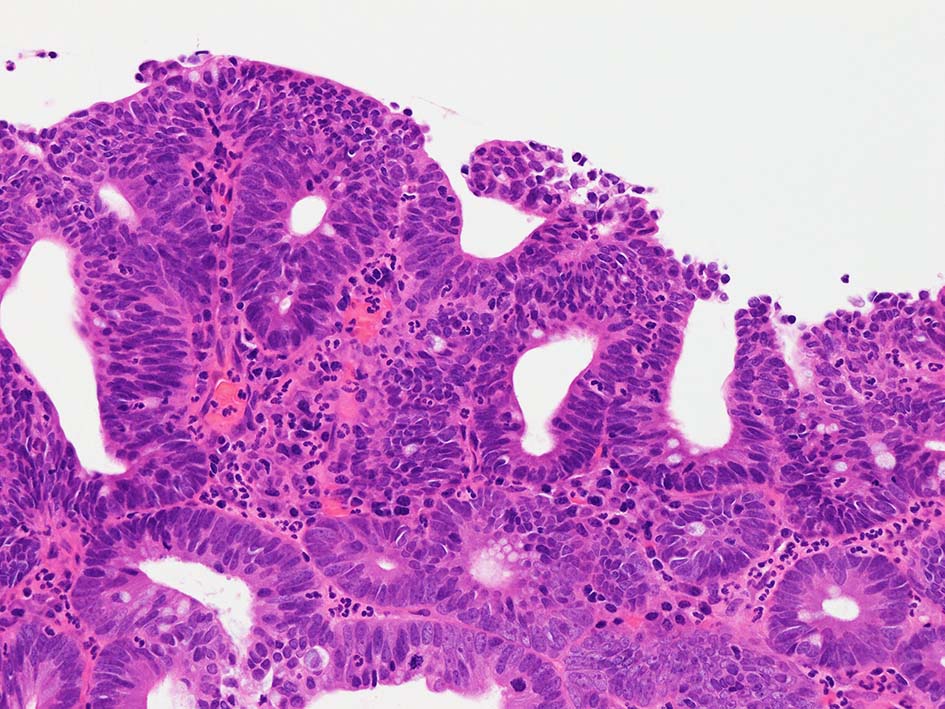

neutrophilic exudate の付着する腸管型腺癌部分. 核はより腫大し円形、vesicularとなっている. 上記腸管型とはCK20, CK7のそまりが異なっていた. 変性のためかもしれない.